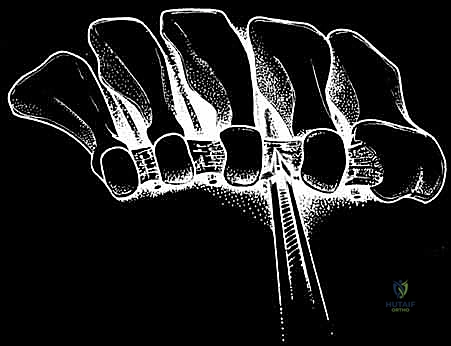

TECH FIG 1 • Surgical technique for uniportal endoscopic decompression of the intermetatarsal nerve. Cannula is in the interspace just plantar to the transverse intermetatarsal ligament and dorsal to the intermetatarsal (interdigital) nerve. The transverse intermetatarsal ligament is being transected from distal to proximal. (Courtesy of AM Surgical.)